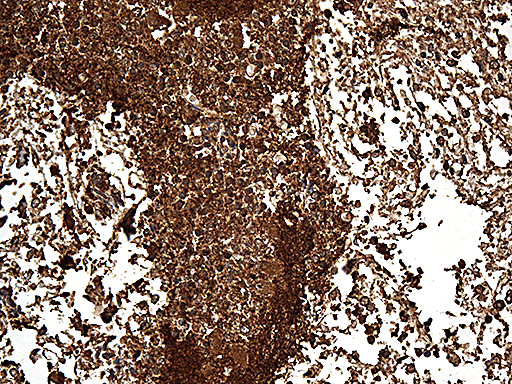

IHC analysis of SNCA using anti-SNCA antibody (BM4024) .

SNCA was detected in a paraffin-embedded section of human colon cancer tissue. The tissue section was incubated with rabbit anti-SNCA Antibody (BM4024) at a dilution of 1:200 and developed using HRP Conjugated Rabbit IgG Super Vision Assay Kit (Catalog # SV0002) with DAB (Catalog # AR1027) as the chromogen.